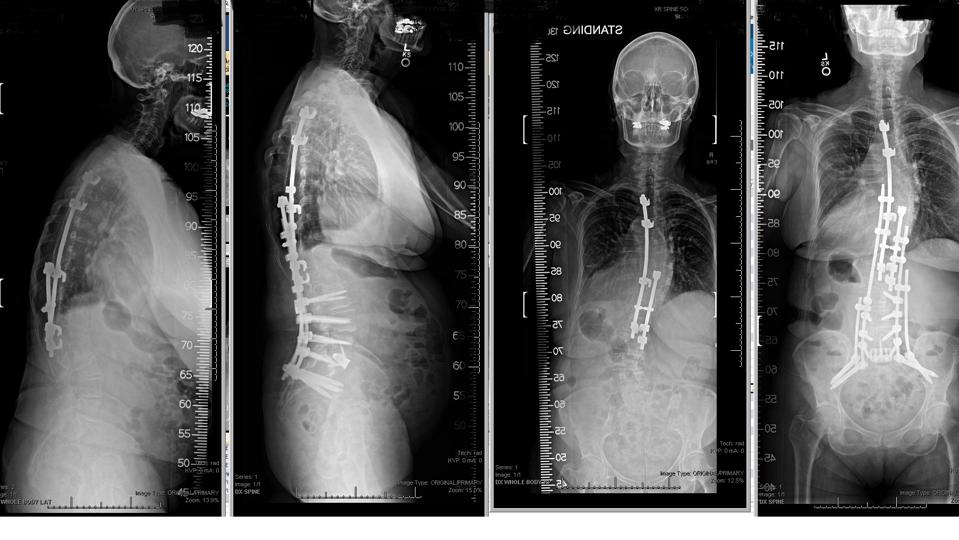

This patient, who received an older spine instrumentation technique during childhood, later … More

In more severe cases, surgical options may be proposed to correct the scoliosis curve and restore balance to the thorax, creating vital space for the heart and lungs within the chest cavity. These procedures typically involve the use of rods, screws, and precise bony carpentry, such as osteotomies, to realign the spine. The rigidity or inflexibility of the curve directly influences the complexity of the surgery, with more rigid curves often requiring more extensive osteotomy bone cuts to achieve proper alignment.